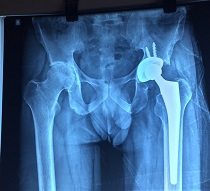

Bilateral Thr

Bilateral Thr Male

Preop AP View